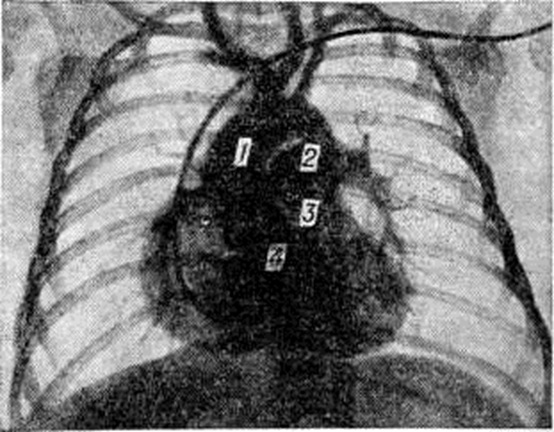

Рис. 2.

Ангиокардиограмма при тетраде Фалло (переднезадняя проекция): рентгеноконтрастное вещество введено в правый желудочек, наблюдается одновременное патологическое контрастирование аорты (1) и лёгочного ствола (2), устье которого (3) сужено, луковица аорты (4) смещена вправо.

Важное значение для окончательной диагностики Фалло тетрада, определения степени нарушения гемодинамики и уточнения анатомических изменений имеют дополнительные исследования — катетеризация полостей сердца (смотри полный свод знаний: Катетеризация сердца) и ангиокардиография (смотри полный свод знаний). Результаты этих исследований необходимы для решения двух важных практических вопросов — определения показаний к хирургическому лечению и выбор оптимального типа операции.

Ангиокардиографию необходимо выполнять в двух проекциях: переднезадней и боковой. Рентгеноконтрастное вещество вводят через катетер, расположенный в полости правого желудочка. На первых же кадрах ангиограммы выявляется основной признак порока — одновременное поступление рентгеноконтрастного вещества в лёгочный ствол и аорту (рисунок 2). Наряду с этим выявляется стеноз лёгочного ствола, который наиболее чётко может быть определён в боковой проекции. Когда при анализе ангиограмм, выполненных таким путём, возникают подозрения на существование дополнительных уровней стеноза на протяжении лёгочного ствола, необходимо проведение дополнительного исследования в аксиальной проекции.